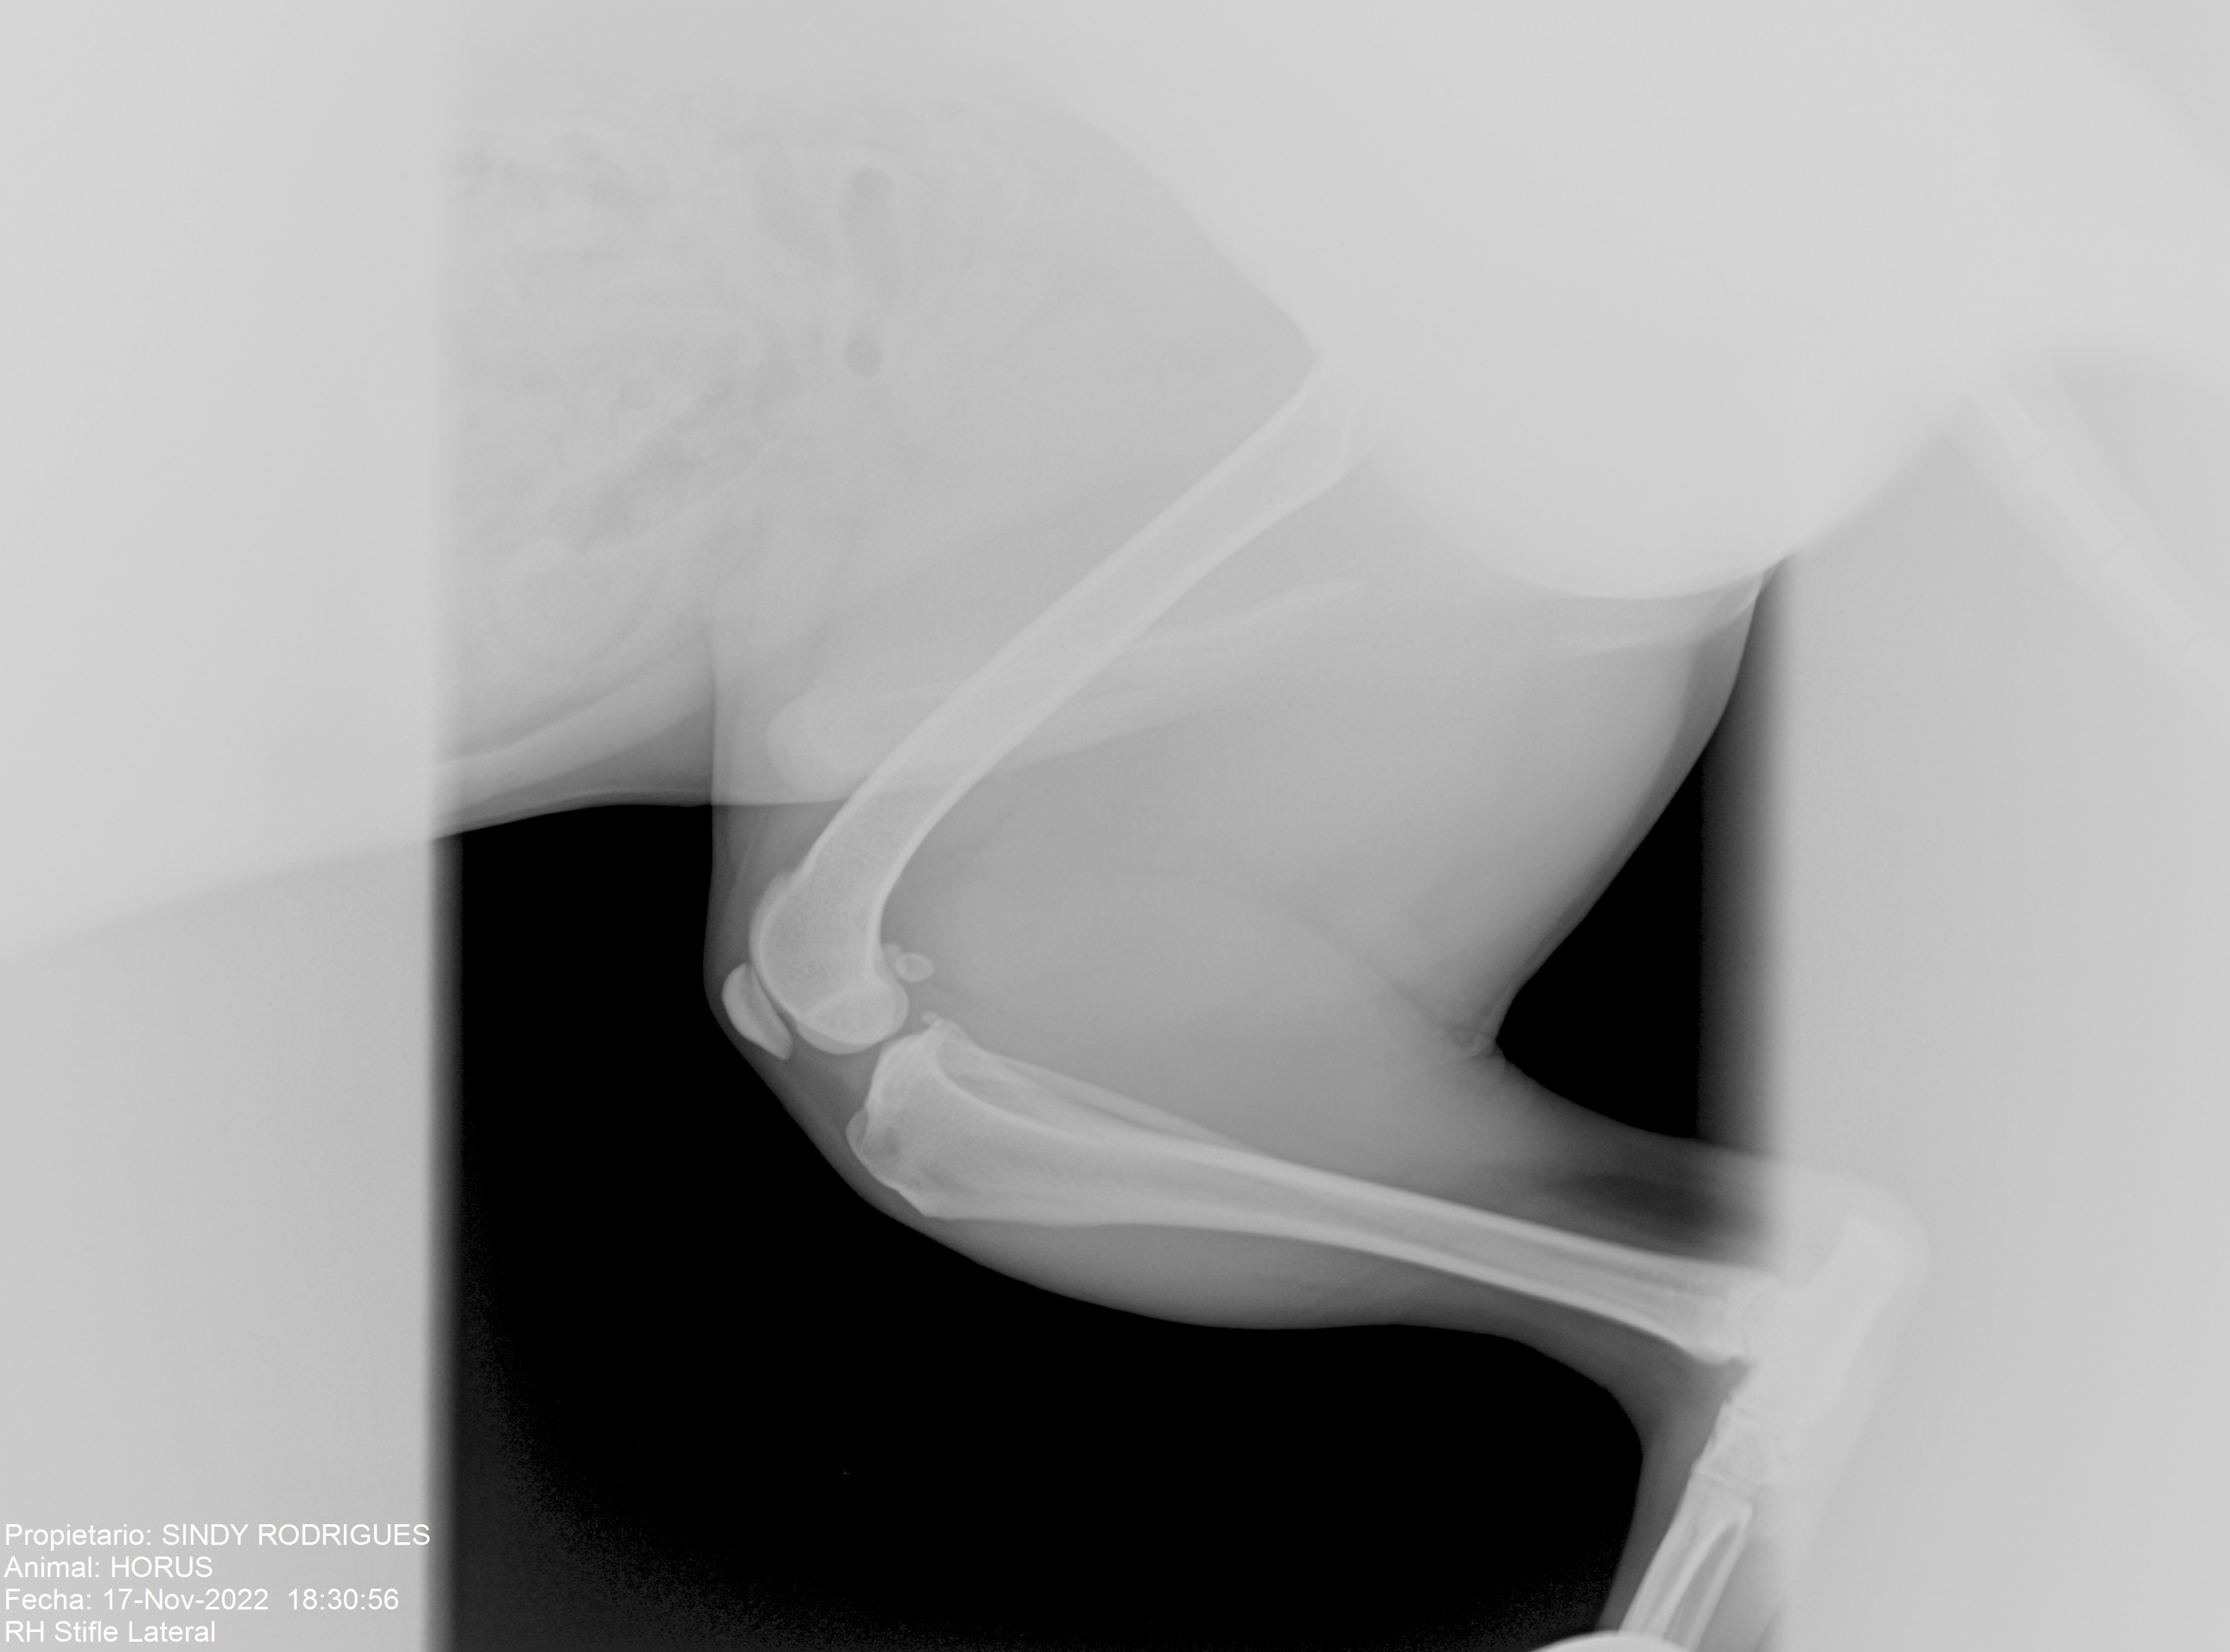

Hola me llamo Horus, he sufrido una ruptura de ligamento cruzado de mi patita izquierda y necesito operarme cuanto antes para no forzar mi otra patita y que no me pase igual, y estoy buscando echar una patita a mis papis para poder hacerlo cuanto antes, gracias a todos a los de buena voluntad.